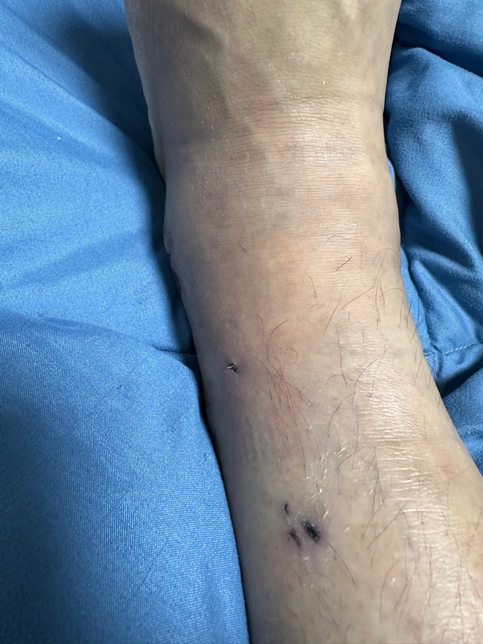

- 의료법률노련한참밀드리138골절 수술 후 체내 쇳조각이 살을 뚫고 나옴12/11 발목 골절 수술(심 박는) 받았습니다 수술 진행 후 엑스레이도 찍고 무사히 잘끝났다는 말에 안심하고 시간을 보낼 수 있었습니다 그리고 일주일간 입원 후 퇴원한 뒤 수술한지 2주가 지난 시점 지금까지 감고 있던 붕대를 풀고 집으로 돌아간 뒤 확인해보니 저렇게 낚시바늘같은것이 살을 뚫고 나와있었습니다당장 주말과 크리스마스연휴라 내원을 하지 못하고 몇일이 지나 내원을 했더니 이런 쇳조각이 몸안에서부터 살을 뚫고 나왔던겁니다자초지종을 물어보니 심을 박는 과정에서 판과 심의 마찰때문에 해당 쇳조각이 생성이 되었다고 하더라구요 백번 양보해서 쇳조각이 생성될 수도 있지만 이대로 봉합했다는 사실이 충격이었구요 설마 알면서 그랬다고는 상상하기싫고 몰랐다는것도 상상하기 힘듭니다 해당 엑스레이를 그당시에는 설명안하고 제가 내원했을 때 설명하시더라구요 "여기선 잘 안보여" 라고 하는데 일반인인 제가 여기있다고 말씀드렸습니다. 심지어 다른각도에서는 더 잘보이구요. 그래놓고 허겁지겁 다음 예약 잡자 말을 돌리시더라구요마지막에는 진료비까지 내라 하시던데 해당 내용 제가 보상받을 수 있을까요1명의 전문가가 답변했어요